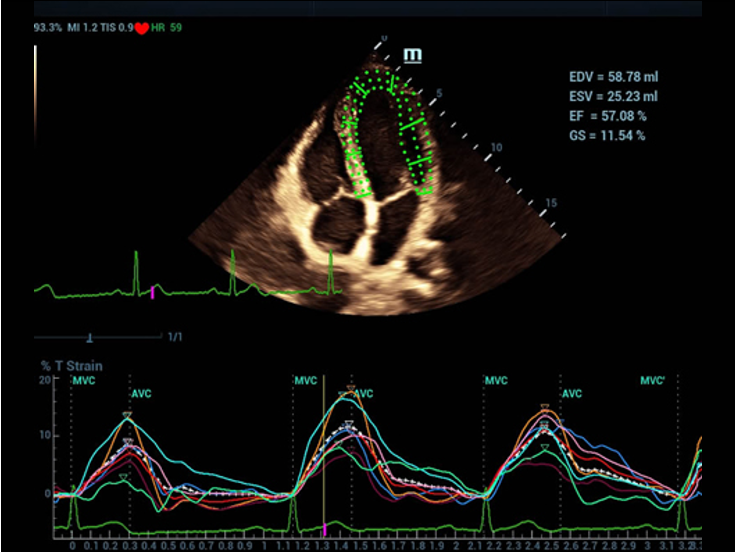

Fin dalla sua fondazione Mindray esplora continuamente nuovi modi per migliorare l'affidabilit├Ā diagnostica. Equipaggiata con la pi├╣ rivoluzionaria tecnologia ZONE Sonography?, la nuova piattaforma ZST+ di Resona 7 porta la qualit├Ā dell'immagine ecografica ad un livello superiore con l'acquisizione per zone e l'elaborazione dei dati canale.

Oltre alla qualit├Ā delle immagini di livello eccellente, Resona 7 migliora anche le capacit├Ā di ricerca clinica il rivoluzionario V Flow per la valutazione emodinamica vascolare, e l'acquisizione piani pi├╣ intelligente dal set di dati 3D per la diagnosi del sistema nervoso centrale fetale. Combinando il pi├╣ intuitivo funzionamento multi-touch basato su gesti e tutte le caratteristiche cliniche essenziali, Resona 7 sta veramente portando nuove tendenze nellŌĆÖinnovazione dellŌĆÖecografia.